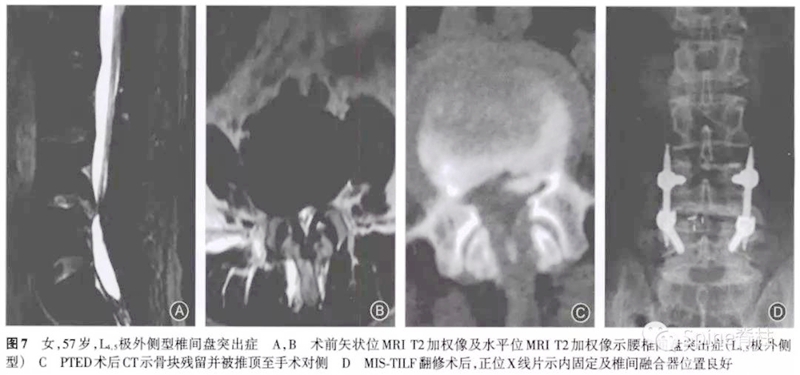

病例七

所有7例患者在经皮内镜手术中均进行了椎间孔成形操作。5例为术后立即出现症状,1例为术后1周出现症状,1例为术后1个月出现症状。经保守治疗后,1例患者症状好转拒绝手术,2例出现对侧的刺激症状,余4例均为原症状加重。其中因残留骨块刺破硬膜囊出现脑脊液漏者2例,残留骨块损伤神经引起下肢肌力下降1例。术后CT提示5例骨块在椎问孔成形同侧,2例在对侧。

术后至翻修时间最短为2d,最长为3个月。翻修术式:2例为椎间盘镜手术,1例为可动式椎间盘镜手术,1例为小切口开窗减压术,1例为经皮内镜手术,1例为微创经椎间孔入路腰椎椎体间融合术。